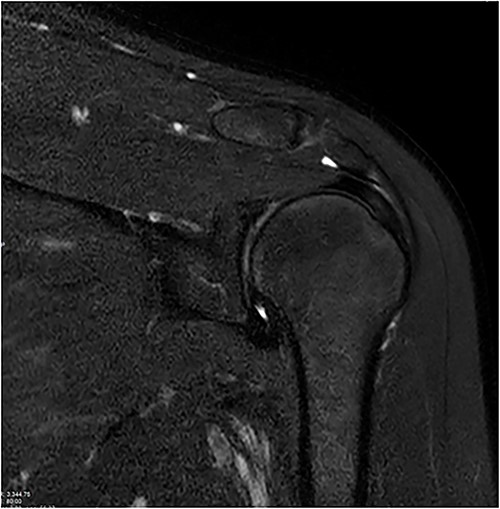

Standard anterior/posterior and lateral X-rays of the affected shoulder were done. The patient was diagnosed with adhesive capsulitis. She was therefore referred to office-based extensive rehabilitation program to improve range of motion and strengthen shoulder muscles. Though MRI does not play a rule in the diagnosis and management, we opted to do one, after consenting the patient, trying to understand the peculiarity of the case (Figs 1 and 2).

Coronal and axial T2 fat saturated image of left shoulder showing thickened inferior capsule of low T2 signal, characteristic of the freezing phase in adhesive capsulitis.